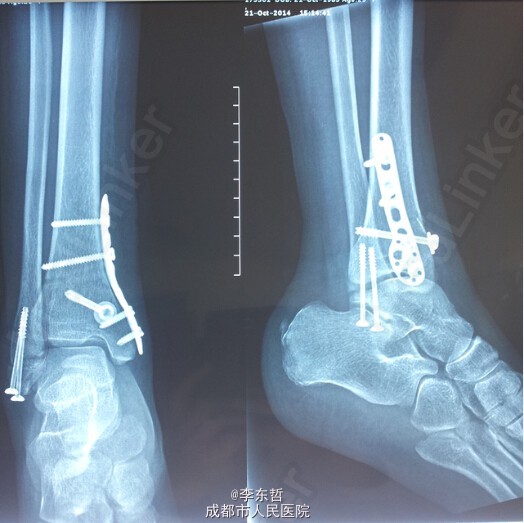

左下肢胫腓骨骨折伴右下肢内外踝骨折一例

患者,女,26岁,外伤致左下肢胫腓骨骨折、右下肢内外踝骨折,入院后右侧临时石膏固定、左侧骨骨牵引10天后,双侧同时手术,左侧胫骨采用MIPPO技术内侧钢板固定。